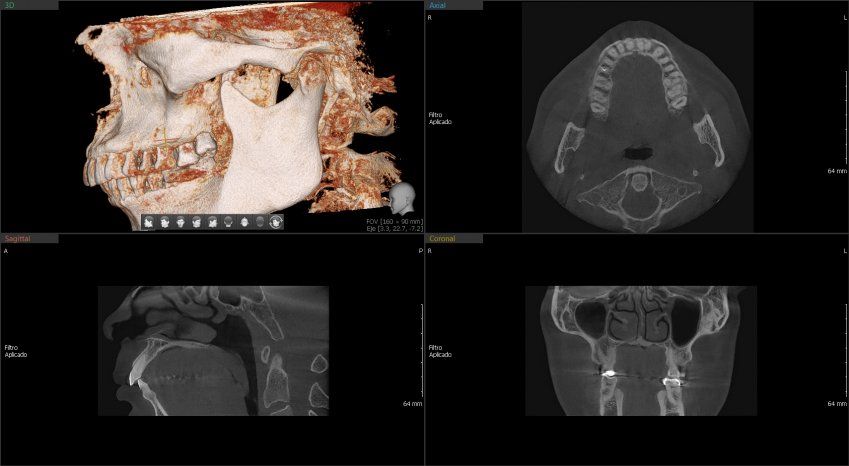

Green 16/18 ofrece una gama de campos de visión seleccionables. Multi FOV permite al usuario seleccionar el modo FOV óptimo y minimizar la exposición a áreas que no son la región de interés. Seleccione el tamaño adecuado de FOV entre 16×9/18×10, 12×9/13×10, 8×9 y 5×5 basado en una particular necesidad de diagnóstico.

Cubre la región del arco completo, seno y la ATM izquierda / derecha y es adecuado para la mayoría de los casos de cirugía oral así como la cirugía de implantes múltiples. También puede medir el volumen de la vía aérea.